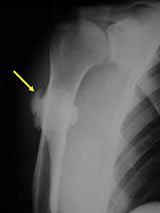

Sites:

- Posterior distal femur metaphysis (65%)

- Presents as a mass in popliteal fossa

- Proximal humerus (15%); Tibia (10%); Fibula (3%), Radius, Ulna

- Lobulated and ossified exophytic mass (cauliflower-like) adjacent to the cortex; attached to metaphyseal cortex via a broad base

- Firm, exophytic bony mass fixed to cortex by means of a broad base

- Grows along long axis of bone and around the circumference of the bone